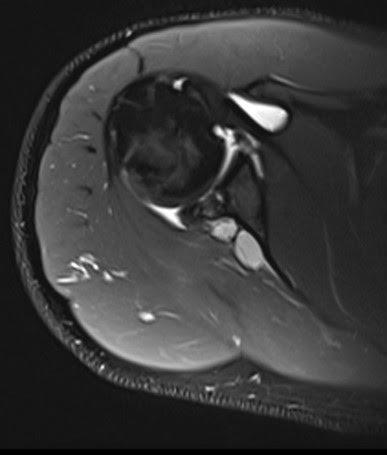

Figura 2: Secuencia axial PD-FS: quiste bilobulado en la escotadura espinoglenoidea.

3:

Figura

Secuencia sagital PD-FS: incremento difuso de la señal miofibrilar del músculo del infraespinoso por probable denervación.